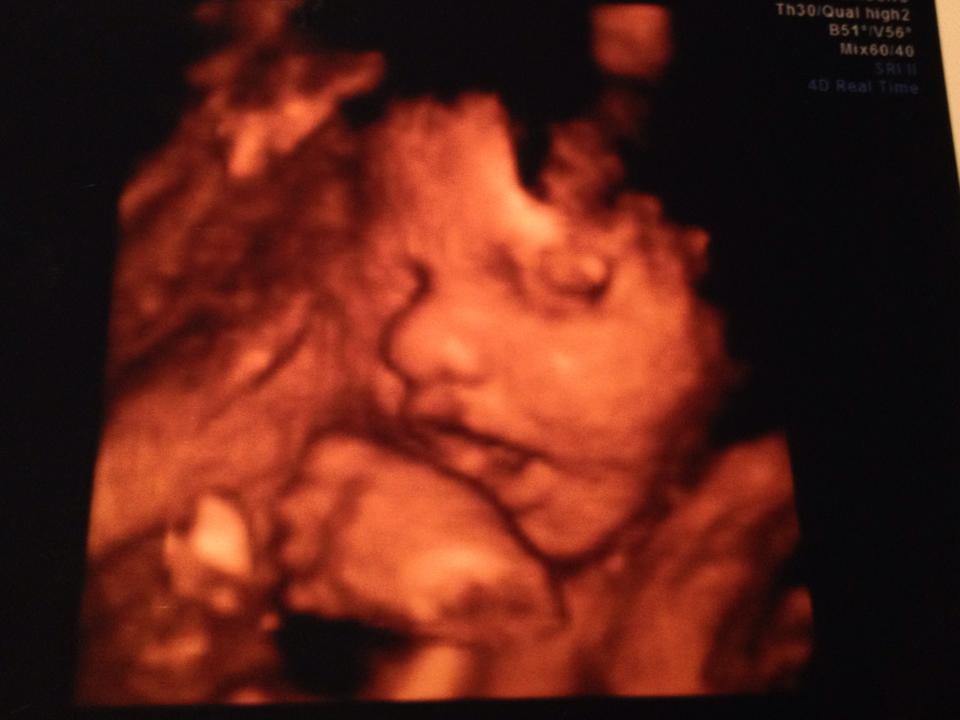

went for my 3D sono last night...

and cannot say enough good things about Little 3D Wonders. They were so friendly, didn't rush through, and the office made me feel so comfortable.

I went in thinking I was going to do a lower package and decided to go all out once I got in there…picture frame, stuffed animal with heartbeat, 1/2 hour package, etc.

I was also opposed to doing it in the beginning and wouldn't trade this experience for anything!

Here is my little girl (I can't stop staring)